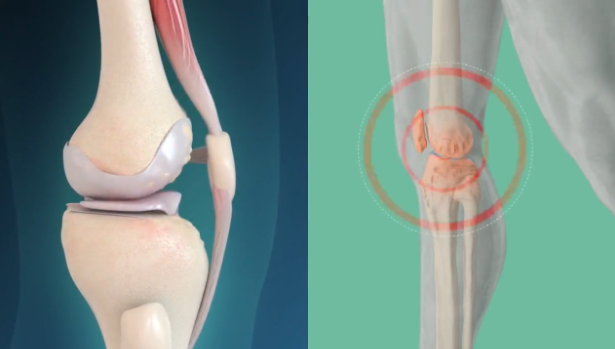

Our joints are crucial for mobility, bearing the brunt of our daily activities. They act as shock absorbers, cushioning the impact from walking, climbing stairs, opening jars, and all the movements you do every day.

As cartilage wears away over time, bones start rubbing against each other, causing that grinding, bone-on-bone pain. This friction leads to inflammation, swelling, stiffness – especially in the morning – and a significant reduction in your mobility and independence.

Mesenchymal cells are the only cells in your body capable of transforming into new cartilage, new bone, and new joint tissue. They're like specialized construction workers that can become whatever your joints need to repair themselves.